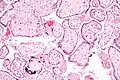

![]() Микрофотография плацентарной инфекции (плацентарный ЦМВ) | |

Инфекцию можно выявить микроскопически путём обнаружения внутриядерных включений. При окраске гематоксилин-эозином тельца включений становятся темно-розовыми, их называют «совиными глазами»[9].

Микрофотография цитомегаловирусного плацентита.